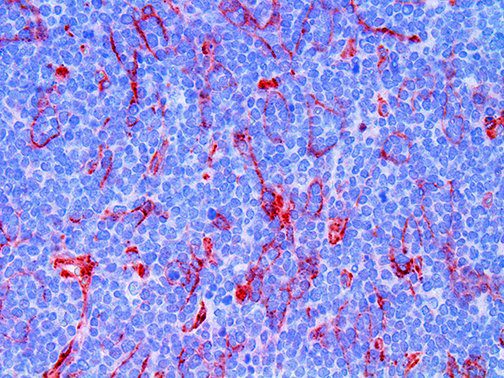

The first cytokines released are interleukin 1β (IL-1β) and tumor necrosis factor-α (TNF-α), which attract a variety of circulating white blood cells (WBCs) to the infection site, including neutrophils, monocytes, macrophages, and natural killer (NK) cells. This response, along with the antipathogenic chemicals released by these cells (i.e., complement), comprise the innate immune response. These cells directly attack the invading pathogen and also release additional cytokines, chief among them interleukin-1 and 6 (IL-6). IL-6 is essential for invoking the adaptive immune response, which calls T-cells, B-cells, and T helper (Th) cells to the infection site. IL-6 also stimulates further recruitment, proliferation and activation of macrophages.

This activation induces inflammatory monocytes to highly express IL-6, starting a localized and then systemic cascade effect that results in hyperproduction of IL-6, which accelerates the inflammatory process. Because IL-6 also increases vascular permeability, excessive levels cause blood vessels to become very leaky. This, along with clotting factors released from vascular endothelial cells, stimulates the coagulation cascade, resulting in microthrombosis (tiny clots), which leads to ischemia and tissue death of the kidney, intestines, heart, liver, brain and extremities.